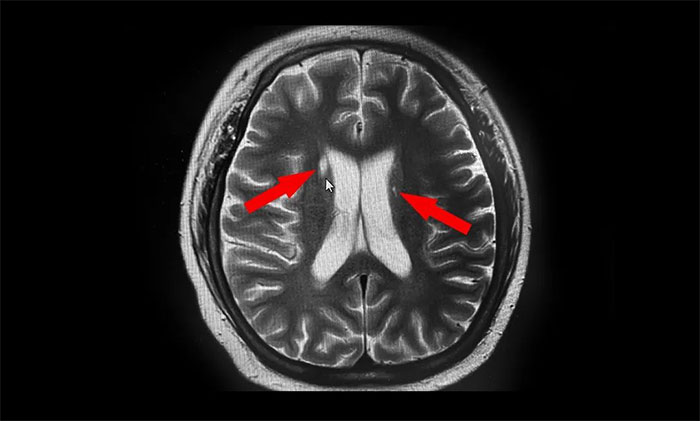

▲ 磁共振檢查影像

磁共振檢查示,阿泰右側尾狀核頭部、左側豆狀核部都有高密度影,這兩處與錐體外系各核團緊密聯(lián)系,協(xié)同隨意運動肌張力和姿勢平衡,也參與復雜運動,因而考慮其為神經(jīng)損傷后錐體外系癥狀表現(xiàn)。